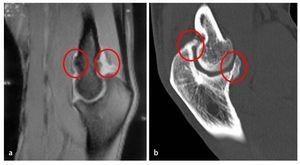

- Diagnóstico radiológico ampliado en caso de dudas especiales: tomografía por resonancia magnética, por ejemplo, para comprobar la presencia de cuerpos libres articulares (fig. 4a).

- Tomografía computarizada, por ejemplo, para la valoración de las superficies articulares y la localización de osteofitos (fig. 4b).

Fig. 4 a) En la imagen de la RMI se observan osteofitos en la zona del húmero anterior. b) El control mediante TAC muestra la magnitud y la localización de las formaciones osteofíticas.